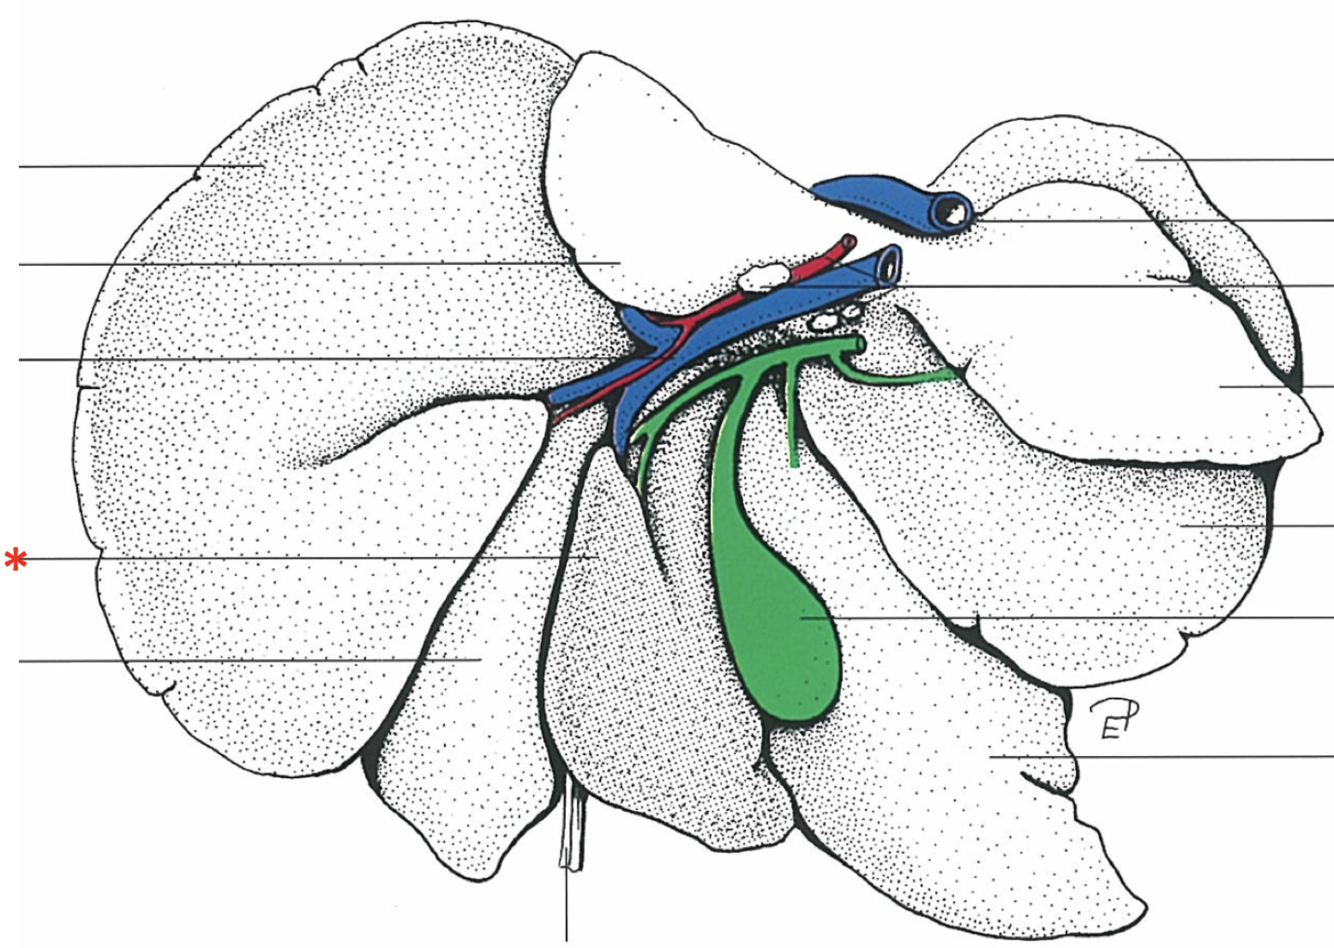

Dorsal Aspect

Area nuda

- Not covered by serous membrane

The Caudate Process extends from the…

Lobus caudatus

The sharp-edged border of the liver is called…

Margo acutus

The blunt-edged border of the liver is called…

Margo obtusus

Ligg.falciformehepatiset tereshepatis

18

Lig. coronale hepatis

15

Lig. hepatogastrica

16

Lig. hepatoduodenalis

- Adjacent to ostium pyloricum

Lig. triangulare sinistrum

Lig. triangulare dextrum

Lig. hepatorenale